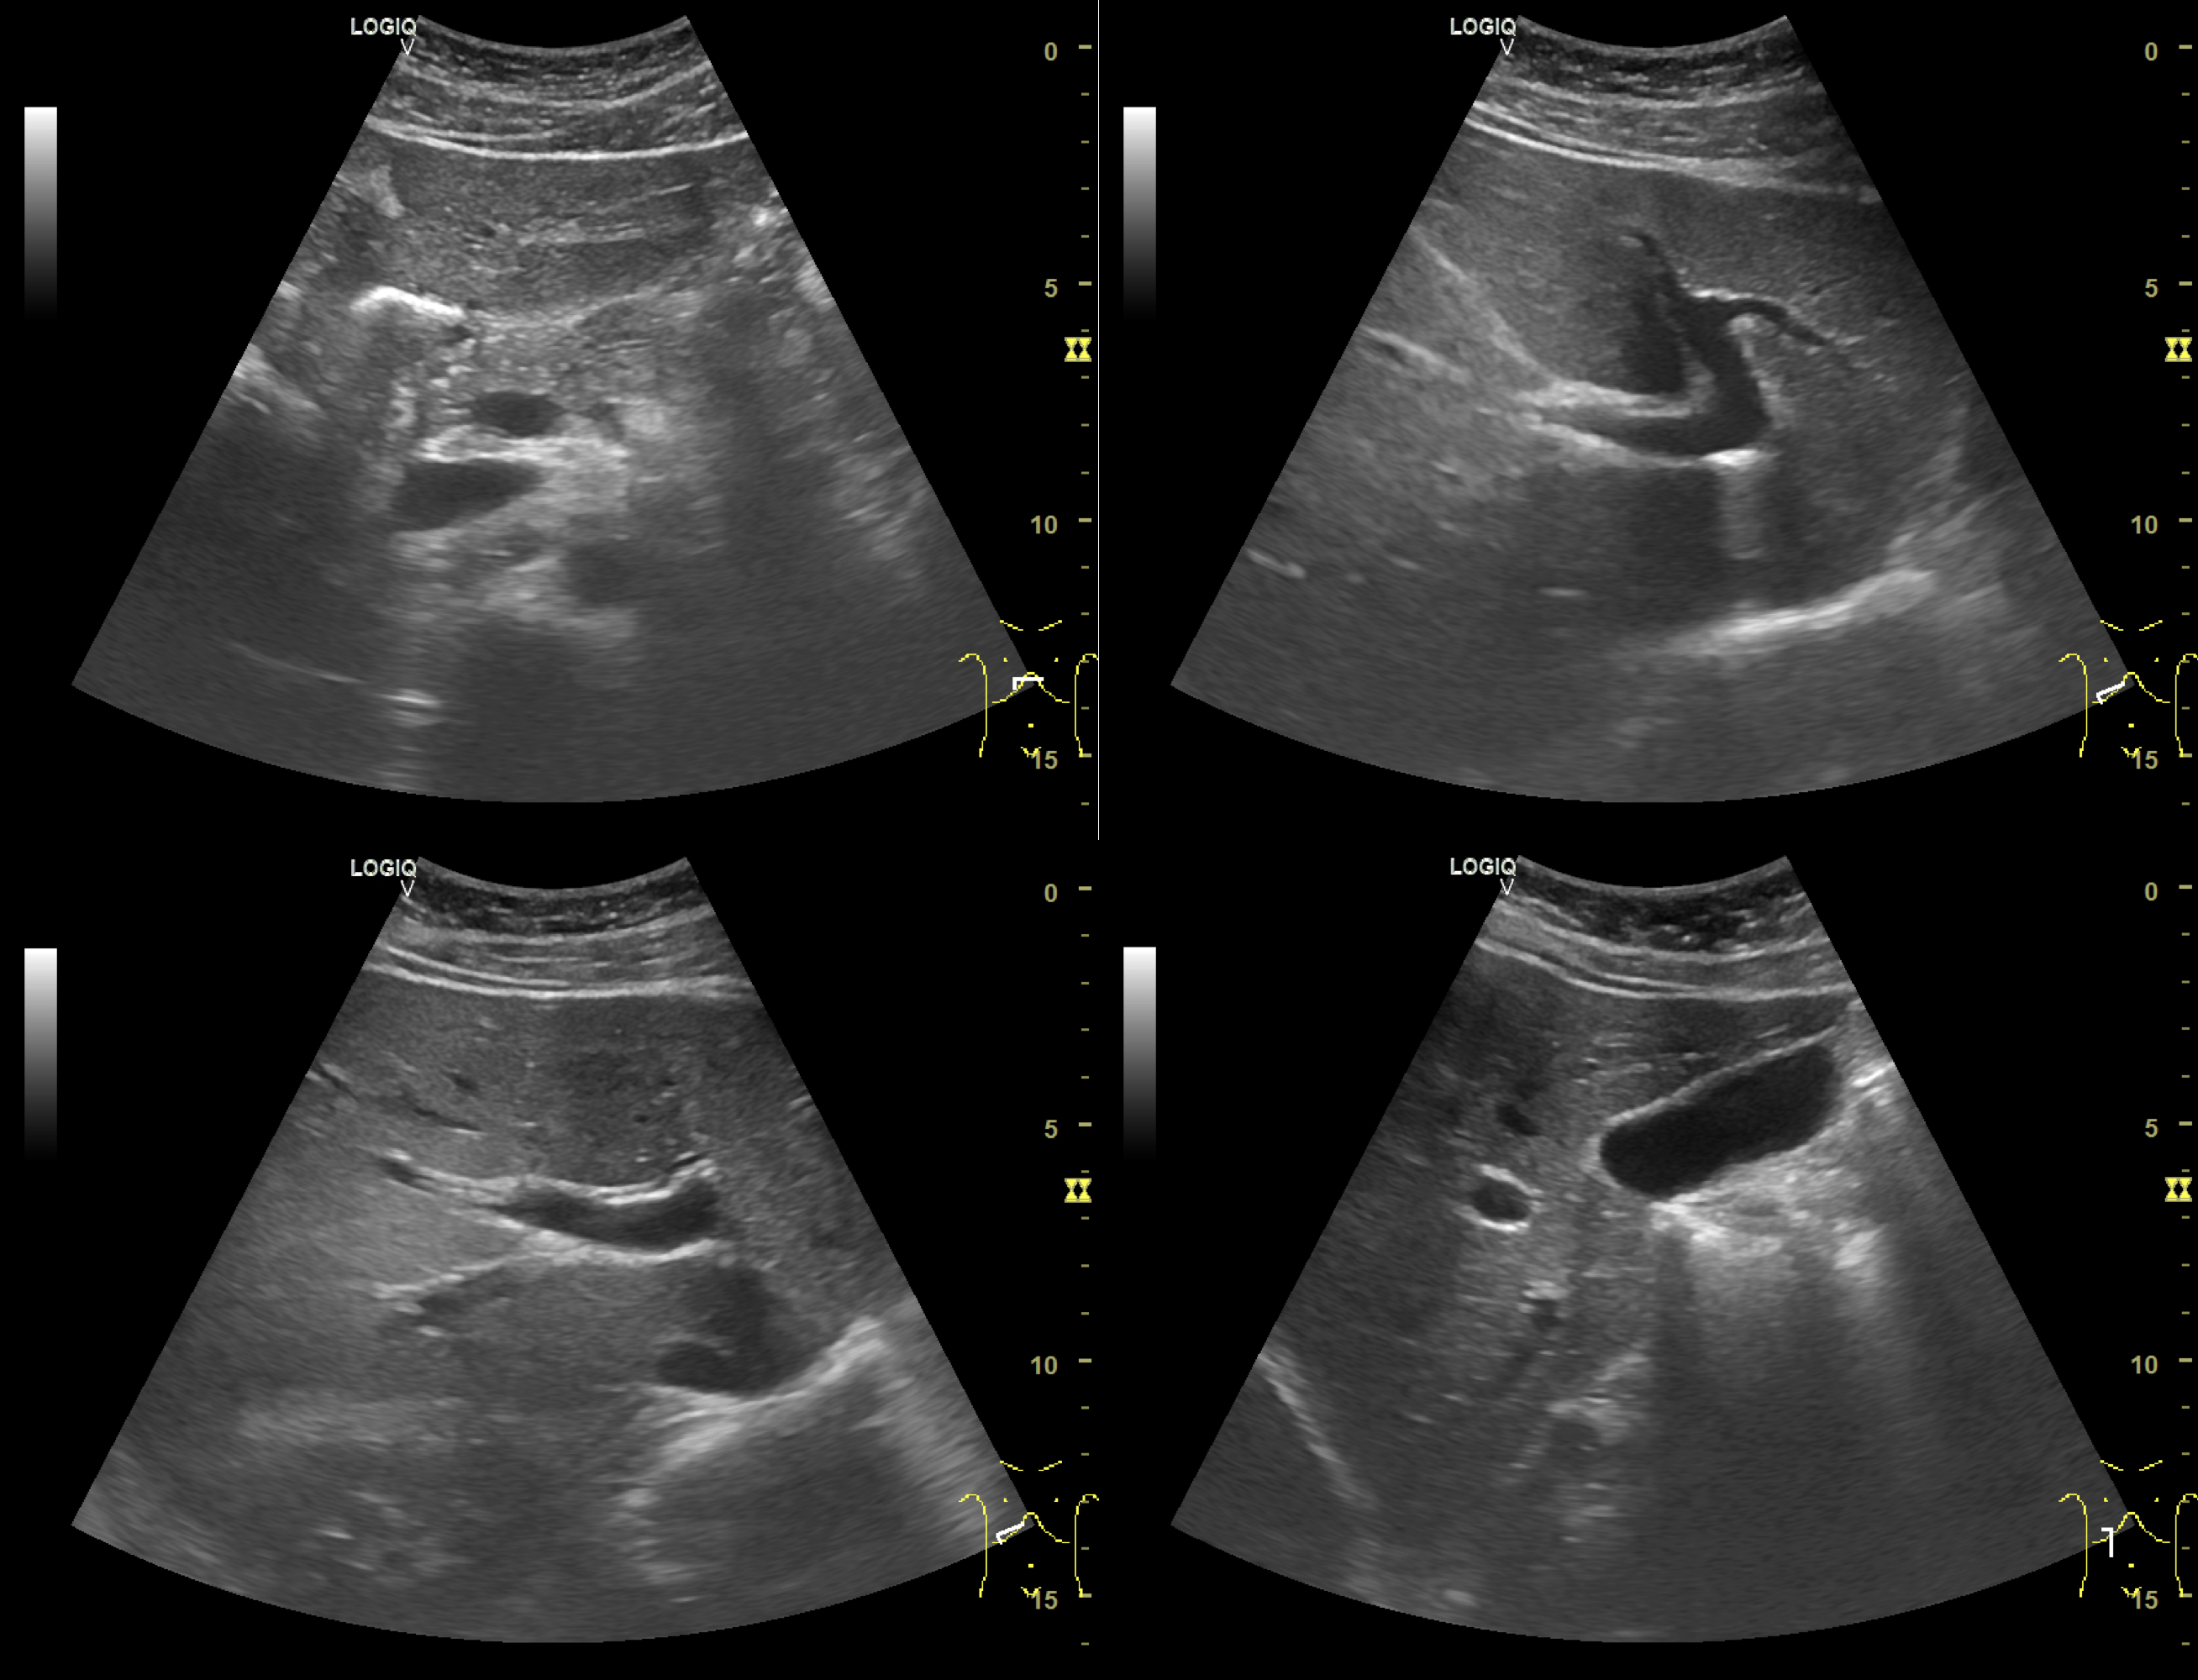

Abdominal ultrasound examination of a foreign patient visiting the Korean Medicine physician's internal medicine clinic

‍

While an abdominal ultrasound showed no specific issues , we diagnosed his condition as 'Dampness Syndrome' (濕證) from a KM perspective.

We began treatment with acupuncture, a Hanyak (herbal medicine) based on Ojeok-san, and crucial dietary corrections. We advised him to reduce grains and fruits, and prescribed a sustainable diet that included cheese, butter, and quail eggs to fit his situation.

After 64 days, his symptoms greatly improved, he had lost 5.6kg, and his body fat percentage returned to the normal range.